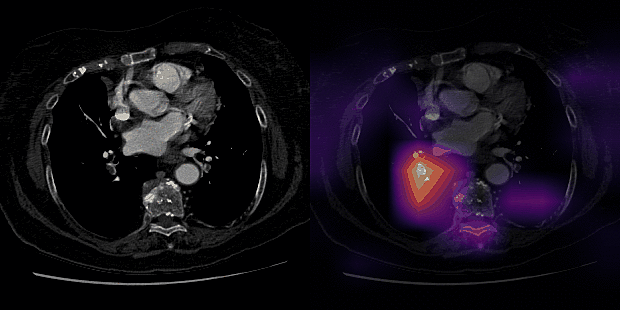

To address this issue, we have curated CTPAs imaging examination from two separate institutions (Stanford and Intermountain) and developed an end-to-end deep learning model, PENet, capable of detecting PE. Some notable implementation details of PENet include 1) pretraining the model with a video dataset (Kinetics-600) for transfer learning and 2) using a sliding window of CT slices as inputs to increase the proportion of the target PE relative to the input. Our model also highlights regions in the original CT scans that contributed most to the model’s prediction, which can potentially help draw Radiologists’ attention to the most relevant parts of the imaging volume for more efficient and accurate diagnosis (see example).